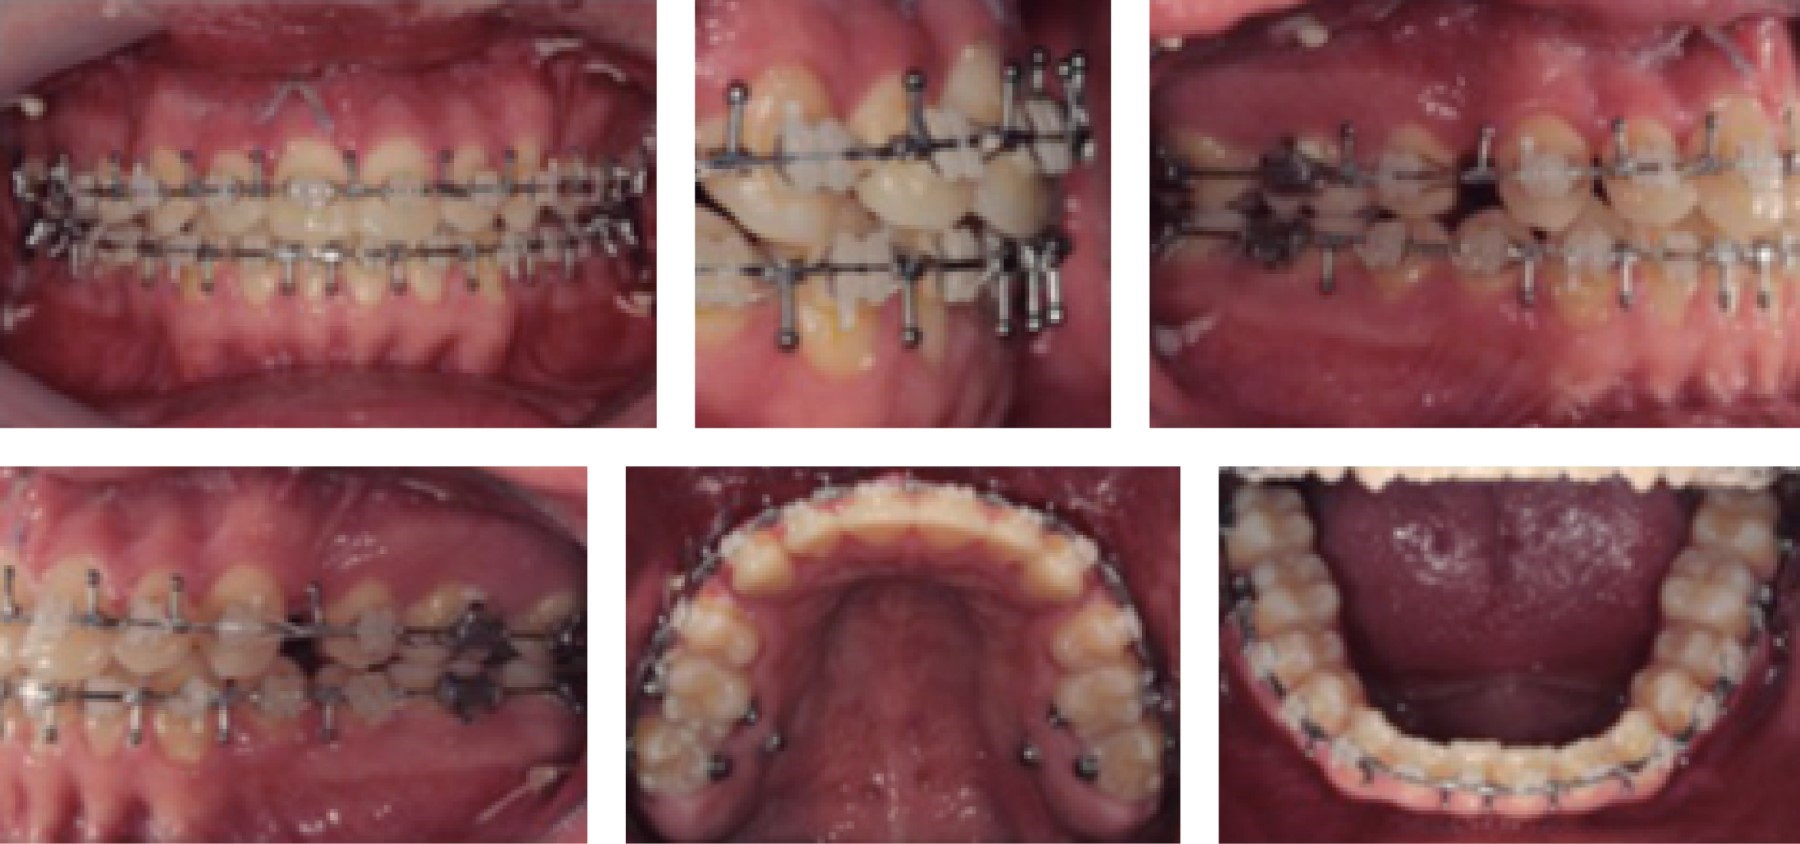

En la actualidad, el paciente se encuentra en tratamiento ortodóncico postoperatorio en fase de cierre de espacios para después continuar con la fase de asentamiento y detallado (Figuras 7, 8, 9, 10, 11, 12, 13 y 14).

Figura 7

Figura 8

Figura 9

Figura 10

Figura 11

Figura 12

Figura 13

Figura 14